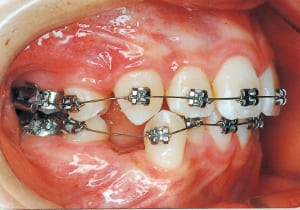

The first phase of treatment involved extracting the left and right maxillary deciduous canines. The space created was used to forcibly retract the four anterior teeth, thereby aiming to improve lip closure function (6–9, 11). Morphological changes suggest that lip function differed before and after treatment (6, 9). Subsequently, the first premolars erupted, but extraction is planned to secure space for canine eruption (10). A Class II molar relationship remains, but the significant overjet has improved (11).

14 After extraction of maxillary bilateral first premolars 11-6-’90

15 At second stage treatment initiation 9-21-’91 Observing eruption of maxillary canines

16 Four months post-second stage treatment initiation 2-29-’92 Currently using headgear on maxill

17 At start of full bracket treatment 5-18-’92

In the maxilla, insufficient space for canine eruption was inevitable, necessitating extraction as part of the treatment plan. The maxillary first premolars on both sides were extracted during routine observation to create space for canine eruption (14). Eventually, the canines erupted and settled into relatively favorable positions (15,19,20). In the mandibular dentition, crowding was also present, leading to extraction of the mandibular first premolars on both sides. Treatment with full bracket was then initiated (17).